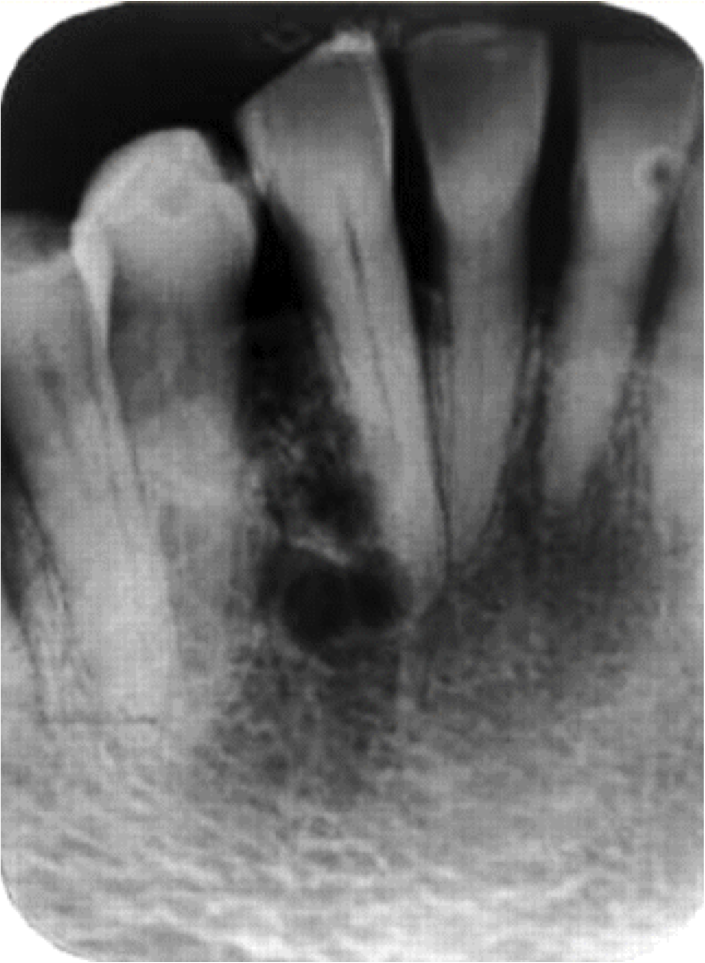

Odontogenic Keratocyst

Tend to grow in an anterior - posterior direction

Doesn’t cause bone expansion

XRAY: Unilocular or multilocular

Corticated margins

Associated GORLIN SYNDROME

Histology:

Thin and friable

Pallisaded and hyperchromatic

Corrugated parakeratin

Daughter cysts